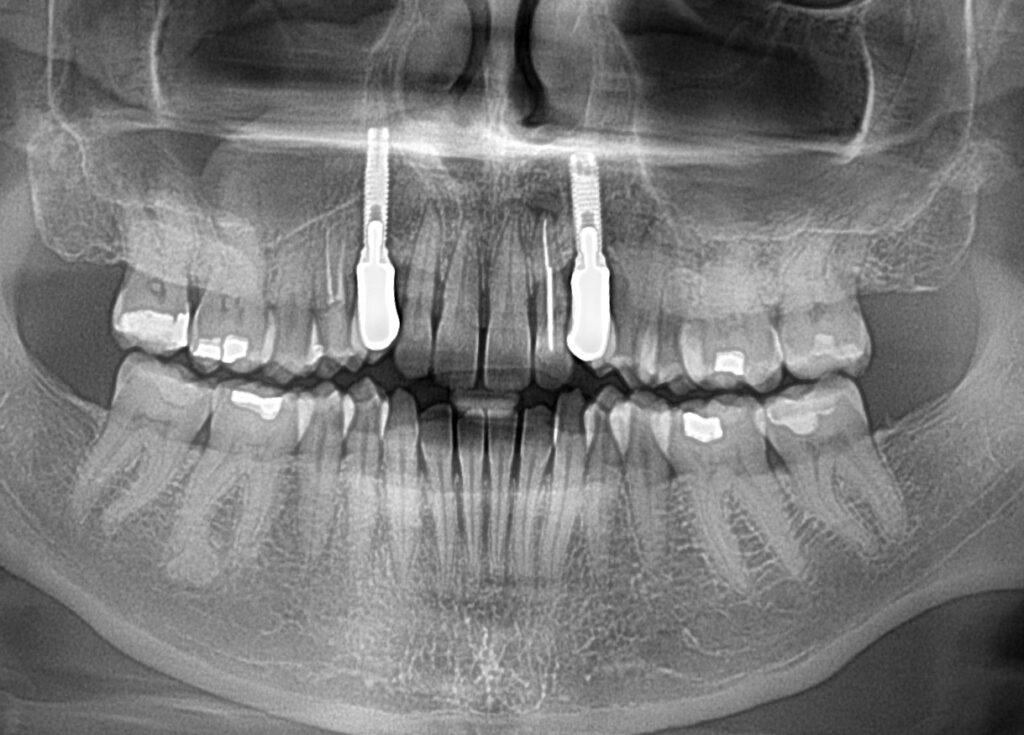

A selection of partial arch fixed implant bridge patients

Oral Surgeons – Dr Han Choi, Dr Sam Goldsmith, Dr Rajiv Rajpal NSOMS

Prosthodontist – Dr Alan Payne NSOMS/Northland Prosthodontics

Dental technicians – Hosaka Takashi, DT Denture Design, Auckland, CJ Park, Project Dentistry, Auckland and Osteon Medical, Melbourne, Australia.